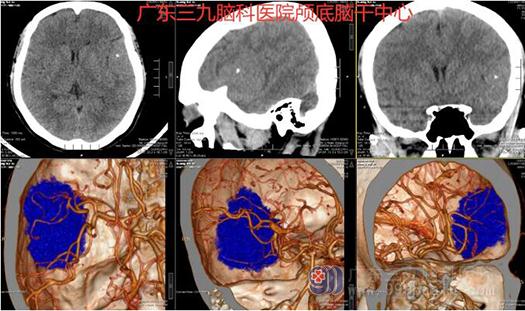

图1:术前CT示左侧颞部颅骨内板下示一占位性病变与颅骨宽基地相连,范围约5.1cm*2.6cm*4.9cm,其内示多发放射状细小血管影,邻近颅骨增厚,左侧大脑中动脉分支受压内移